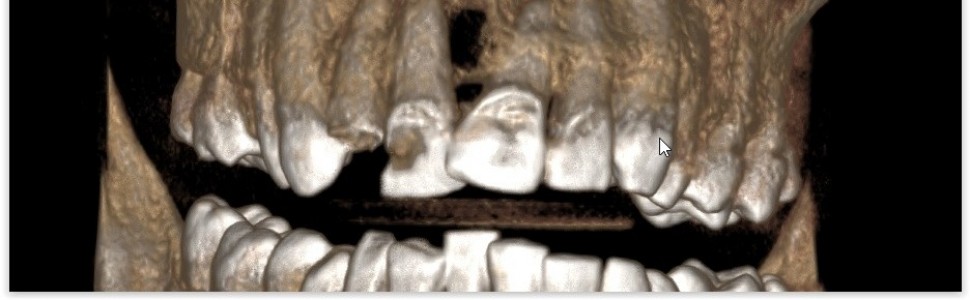

W pracy przedstawiono 2-letnie obserwacje kliniczne u 45-letniego pacjenta, który zgłosił się z powodu dolegliwości bólowych okolicy zębów 12 i 11. W badaniu wewnątrzustnym zaobserwowano trzy bierne, zwłókniałe przetoki w przedsionku jamy ustnej w rzucie wierzchołków korzeni zębów 12, 11 i 21. Wykonane RTG przylegające wykazały m.in.: ząb 11 z rozległymi zmianami okołowierzchołkowymi (widoczne przejaśnienie obejmujące 2/3 długości korzenia zęba 11 od strony mezjalnej i odśrodkowe przesunięcie korzenia zęba 21), korzeń zęba 12 z podejrzeniem resorpcji wewnętrznej i zmianami okołowierzchołkowymi. Ze względu na prośbę pacjenta, a także niechęć do ekstrakcji zębów 12 i 11, pacjentowi przedstawiono możliwość warunkowego leczenia endodontycznego zębów 12 i 11 – z bardzo dużym ryzykiem niepowodzenia oraz konieczność leczenia endodontycznego zęba 21. Przedstawiony poniżej przypadek potwierdza przekonanie, iż leczenie endodontyczne powinno być pierwszym krokiem w przypadku występowania rozległych zmian okołowierzchołkowych – pozwala to uniknąć konieczności przeprowadzenia zabiegu chirurgicznego lub przynajmniej ogranicza

jego zasięg.

The research presents 2-year clinical observations in a 45-year-old patient who presented in dental clinic due to pain in the area of teeth 12 and 11. In the intraoral examination, three passive, fibrotic fistulas in the oral vestibule were observed in the projection of the tips of the roots of the teeth 12, 11 and 21. The performed adjacent X-ray showed, among others: tooth 11 with extensive periapical changes (visible lightening covering 2/3 of the root length of tooth 11 from the distal side and centrifugal displacement of the root of tooth 21), root of tooth 12 with suspected internal resorption and periapical lesions. Due to the patient’s request, as well as reluctance to extract teeth 12 and 11, the patient was presented with the possibility of conditional endodontic treatment of teeth 12 and 11 – with a very high risk of failure, and the need for endodontic treatment of tooth 21. The case presented below confirms the belief that endodontic treatment should be performed as the first step in the case of extensive periapical changes – it avoids the need for surgery or at least limits its scope.

Film 1. CBCT – przekrój osiowy, kwiecień 2019 r.

Film 2. CBCT – przekrój czołowy, kwiecień 2019 r.

Film 3. CBCT – przekrój osiowy, kwiecień 2022 r.

Film 4. CBCT – przekrój czołowy, kwiecień 2022 r.